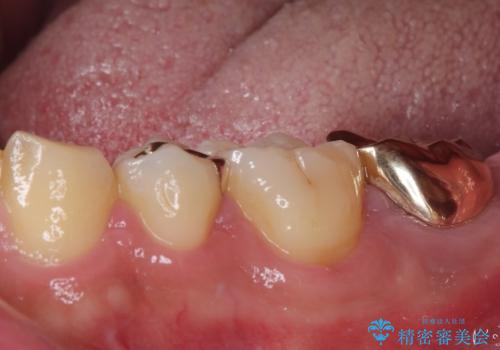

伸び出してきた上顎奥歯 部分矯正を用いた奥歯の補綴治療

- 下顎奥歯のむし歯治療を希望して来院された患者様です。

対合の上顎の奥歯は、むし歯で欠損した部分と咬み合うように伸び出してきていました。

下顎のむし歯の範囲が広く、既に神経は失活しており、根管治療が必要な状態でした。

上顎の歯をアンカースクリューを用いた部分矯正により位置を修正し、根管治療後にPGAクラウンにて補綴治療を行うこととしました。